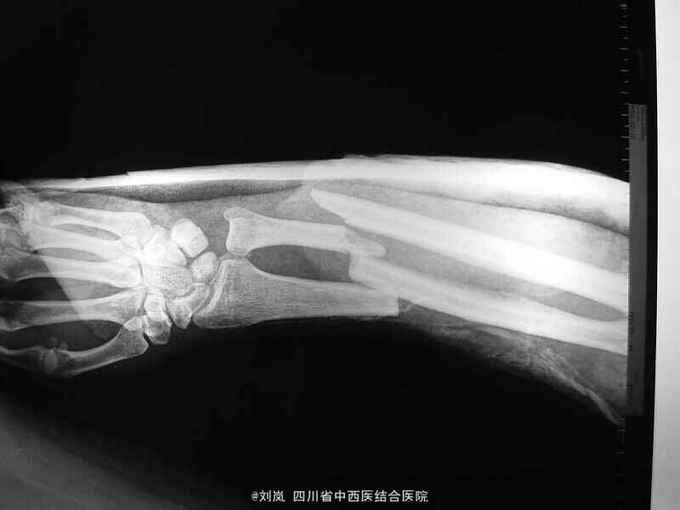

查体:T 37.9℃、P 110次/分、R 22次/分、BP 126/80mmHg;一般情况:神清,烦躁,发育正常,平车推入,查体不合作。头额顶部见横行挫伤,头皮肿胀、压痛明显,未扪及骨擦感,右上下睑肿胀青紫,左面部见擦挫伤,双侧瞳孔等大等圆,直径约3mm,对光反射迟钝,鼻腔无溢液,左耳廓见擦伤,外耳道无异常分泌物,双唇肿胀,无紫绀及苍白,齿齐,扁桃体不大,颈软,气管居中,甲状腺不大;胸廓对称无畸型,右侧胸胁部压痛明显,似可扪及骨擦感,呼吸动度基本一致,双肺叩呈清音,双肺呼吸音粗,双肺未闻及干、湿性罗音;心界叩诊不大,心率110次/分,律齐,各瓣膜听诊区未闻及病理性杂音。腹平,未见肠型及蠕动波,未见浅静脉曲张,肝脾未扪及,腹肌紧张,压痛,反跳痛明显,无移动性浊音,肝肾区无叩痛,肠鸣音3次/分。脊柱下肢无畸型,活动正常,右膝前见一约5cm挫裂伤口,深及髌骨,未扪及骨擦感,右上臂及右前臂夹板外固定中,桡动脉搏动可,末梢循环可,肛门及外生殖器未查,排泄物未见。神经系统检查生理反射存在,病理反射未引出。 患者入院急诊行了剖腹探查术等治疗;2周后外科病情平稳,转骨科治疗。转入查体:头额部无畸形,右眼睑肿胀减轻,仍可见双眼周围青紫瘀斑减轻,两侧瞳孔等大等圆,直径3mm,对光反射灵敏,颈软,无抵抗,布鲁金斯基征(-),双侧胸廓对称,无畸形,双侧呼吸动度一致;腹中度见一大约10cm手术切口瘢痕,已经愈合,切口对合良好,未见异常渗血渗液,右下腹原引流管拔除处创口未愈合,经换药可见创口大约1.5*2.5cm2,创口基底部乳白色分泌物,无血性及脓性分泌物,创口周围轻微肿胀,无皮色改变,无皮温升高,无波动感,压痛(+),无反跳痛,无肌紧张,无移动性浊音;骨盆分离挤压试验(- );右上肢石膏托固定良好,拆开石膏见:右上臂外侧见一大约2*2.5cm的创口,周围无红肿,无皮温皮色改变,创面红润,未见异常渗血渗液,未见骨质外露,右上臂中段及右双前臂中下段畸形,压痛明显,可触及明显骨擦感及异常活动,右上肢纵向叩击痛(++),右上肢及右前臂旋转功能活动障碍,右腕关节及右手拇指不能主动背伸活动,右前臂中下段以下皮肤感觉功能障碍,右手呈轻度屈曲挛缩畸形,无法主动伸直及主动握拳,指端血运正常。 辅助检查: DR示:1.腹腔内游离气体 2.右肱骨中段骨折 3.右尺桡骨中下段粉碎性骨折。 CT示:1.右侧顶叶点状高密度影,脑挫裂伤?右侧额部及左侧额顶部头皮血肿。2.右肺斑片及斑点状阴影,感染灶?3.右侧约第7、8肋骨可疑骨折。4.腹腔内可疑积气:盆腔可疑少量积液:膀胱内片状较高密度影,积血? 彩色多普勒提示:膈下游离气体,少量腹腔积液。

入院诊断: 1、高处坠落伤 2、脑挫裂伤 3、小肠部分坏死 小肠穿孔 肠系膜挫伤 4、右肱骨中段骨折 5、右尺桡骨中下段骨折 6、腹腔积气 7、右第7、8肋可疑骨折 8、轻度贫血 9、全身多发皮肤软组织挫伤 转入诊断: 1、高处坠落伤 2、右肱骨中段骨折 3、右侧尺桡骨中下段粉碎性骨折 4、脑挫裂伤(右,顶叶) 5、右侧桡神经损伤 6、右侧正中神经损伤 7、右侧尺神经损伤 8、右前臂Volkmann缺血性肌痉挛 9、右侧第7肋、左侧第8肋骨骨折 10、小肠部分切除、小肠修补、阑尾切除术后 11、右膝清创缝合术后 12、腹腔积气 13、轻度贫血 14、全身多发皮肤软组织挫裂伤 治疗: 患者急诊入院后,予完善检查,诊断明确,完善急诊手术准备,急诊在全麻下行了“剖腹探查:小肠坏死部分切除、小肠修补+阑尾切除术+腹腔引流术”,术后在ICU继续抗炎、止血、补液脱水监护对症治疗,并请骨科会诊后予右上肢石膏固定。 术后两周外科病情平稳,再次请骨科会诊后转骨科治疗。转入后进一步完善相关检查及术前准备,诊断明确后,在“全麻”下行了"右肱骨中段骨折切开复位内固定、右尺桡骨中下段骨折切开复位内固定术+植骨术、右侧桡神经损伤探查术",术中见桡神经挫伤明显,局部瘀血及增生组织包裹,予松解处理。术后予消肿、止痛、营养神经、预防感染等对症支持治疗,结合针灸、理疗、中药口服及康复治疗。术后伤口愈合及拆线后,予中药熏洗治疗,配合患肢主被动功能康复锻炼,住院2个月,患肢功能活动明显改善,病情好转出院。